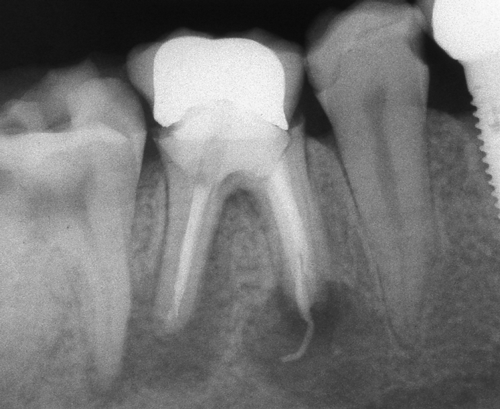

Оралната хирургия е дял от денталната медицина. Понятието орална хирургия е доста условно - с него се обозначават различни видове оперативни интервенции в областта на устната кухина, въпреки че дори и почистването на един кариес по своята същност представлява оперативна интервенция (некректомия); екстирпацията на един нерв от зъбен канал, почистването на зъбен камък, пиленето на зъб за корона и запълването на коренов канал също са оперативни интервенции, понякога технически доста сложни. Все пак всички тези манипулации са извън обема на оралната хирургия - тя включва екстракцията на ретинирани зъби, отстраняването на кисти от зъбен произход, на малки по обем доброкачествени тумори, и, разбира се, поставянето на зъбни импланти. Всички необходими манипулации за осъществяването на костна пластика при имплантатите също влизат в обема на оралната хирургия.